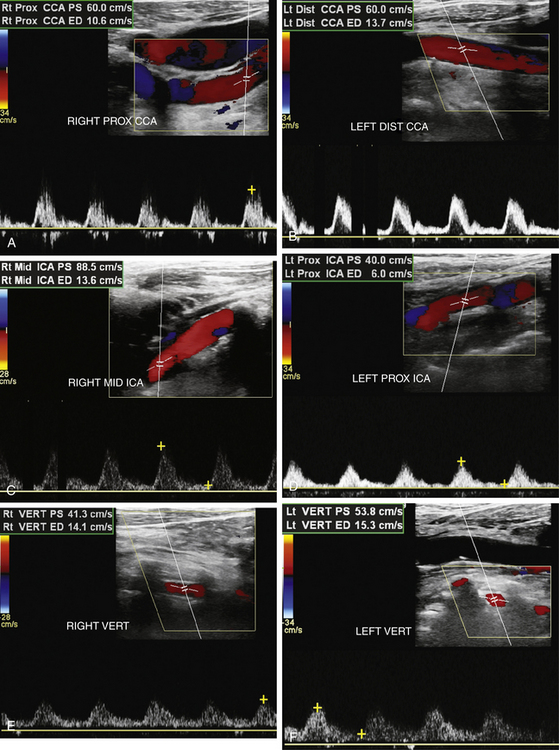

Перед операцией на сердце этому 55-летнему мужчине было назначено скрининговое УЗИ сонных артерий. При серой и цветной визуализации в шейных отделах сонных артерий было обнаружено лишь несколько небольших бляшек. Просмотрите результаты допплеровского исследования, показанные на рисунке 10-14 , и поставьте диагноз.

РИСУНОК 10-14. Случай 4. A и B. Доплеровские спектры правой и левой общей сонной артерии (ОСА). C и D: Допплеровские спектры правой и левой внутренней сонной артерии (ICA). E и F: образцы правой и левой позвоночных артерий (VERT).

Анализ

Допплеровские волны равномерно затухают и напоминают тардус-парвус, а скорость потока низкая во всех областях, что указывает на «глобальное» физиологическое расстройство. Двумя основными причинами являются заболевание аортального клапана и плохая функция миокарда. В данном случае пациент ожидал замены аортального клапана по поводу тяжелого аортального стеноза. Если бы проблема заключалась в тяжелой аортальной недостаточности, на допплеровских кривых можно было бы увидеть характер потока туда-сюда с диастолическим реверсом.

Диагностика

Стеноз аортального клапана, вызывающий глобальное затухание каротидных допплеровских сигналов.

Что следует помнить

1. Общая низкая скорость и затухание обычно вызваны заболеванием аортального клапана или плохой функцией миокарда. Волны Tardus-parvus предполагают проксимальный стеноз, очевидно, вовлекающий грудную аорту, поскольку поражены все ее ветви.

2. Сердечная функция может существенно влиять на результаты каротидной допплерографии. Если бы у этого пациента был стеноз сонной артерии, скорости при стенозе были бы существенно ниже, чем у человека без сердечного заболевания. Как и в случае компенсаторного кровотока (см. Случай 1), соотношения систолической скорости ВСА/ОСА лучше аппроксимируют уровень заболевания, чем пиковая скорость ВСА, используемая независимо.

3. Всегда учитывайте «глобальный» взгляд на физиологию сердечно-сосудистой системы при интерпретации ультразвуковых исследований сонных артерий.